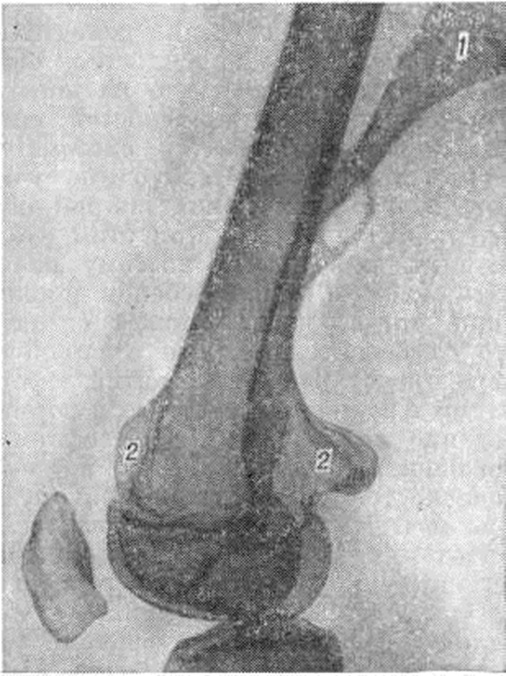

Форма экзостоза, выявляемая при рентгенологическое исследовании, зависит от его локализации. Экзостозы, располагающиеся в проксимальном отделе плечевой кости и в дистальном отделе большеберцовой кости, имеют широкое основание и холмовидную форму (рисунок 6), они как бы распластаны по кости; в их основании много хрящевой ткани. В дистальном метафизе бедра и проксимальном метафизе большеберцовой кости образуются экзостозы с узкой длинной ножкой — линейные экзостозы (рисунок 9). Тело их вытянуто; оно состоит из губчатой кости и обызвествляющегося хряща, на вершине имеется хрящевой чехол. В проксимальном отделе малоберцовой кости, дистальном отделе костей предплечья, в области малого вертела бедра экзостозы имеют шаровидную форму; кости приобретают вздутый, пенистый вид, а многочисленные, сферически располагающиеся отложения солей кальция придают им сходство с цветной капустой (рисунок 10). Экзостозы имеют чёткие контуры за счёт компактной костной пластинки. Структурный рисунок экзостозов веерообразный; главные трабекулы располагаются узким пучком в ножке и как бы рассыпаются к его поверхности. В холмовидных экзостозах структурный рисунок груботрабекулярный. В линейных — более толстые пластинки идут параллельно длиннику кости и поверхности экзостоза. Метафизы костей расширены, удлинены, имеют характерные деформации: вальгусную — в области шейки, проксимального и дистального конца бедренной кости и проксимального конца большеберцовой, варусную — в области костей предплечья. В ряде случаев на рентгенограмме можно обнаружить переломы экзостозов, особенно линейных и шаровидных с узкими ножками. Клинико-рентгенологическая картина множественных экзостозов характерна и не похожа ни на одно другое заболевание скелета. Одиночные экзостозы могут быть приняты за остеому, а при болях — и за остеогенную саркому или хондросаркому, однако рентгенологическое исследование позволяет отвергнуть это предположение. Одиночные экзостозы дифференцируют с гетеротопическими оссификатами и оссифицирующейся гематомой. Указанные патологический образования чаще локализуются у локтевого сустава и не имеют чёткой направленности роста к центру диафиза. Лечение оперативное. Одиночные экзостозы удаляют после их перемещения на диафиз, когда они уже не связаны с эпифизарной зоной роста, повреждение которой может привести к преждевременному её закрытию и деформации конечности. При множественных экзостозах удаляют только те, которые вызывают боль, оказывают давление на сосудисто-нервные пучки, соседние кости или быстро растут. Операция заключается в удалении экзостоза вместе с надкостницей и хрящевым чехлом в пределах здоровой кости. По показаниям, например, при искривлении поражённой кости, удаление экзостозов можно сочетать с корригирующей остеотомией. В случае недоразвития зоны роста или всего эпифиза после удаления экзостоза укороченную и деформированную кость удлиняют и выравнивают с помощью остеотомии или компрессионно-дистракционного аппарата. Эту методику особенно часто применяют при удалении экзостозов, локализующихся в области предплечья и голени. Прогноз для жизни благоприятный. При запущенных больших экзостозах, вызвавших тяжёлые вторичные деформации, прогноз в отношении функции конечности неблагоприятный. На месте больших длительно существующих экзостозов возможно развитие вторичной хондросаркомы (смотри полный свод знаний). При множественной форме заболевания малигнизируется обычно один из экзостозов. Лица с множественными экзостозами подлежат диспансерному наблюдению.